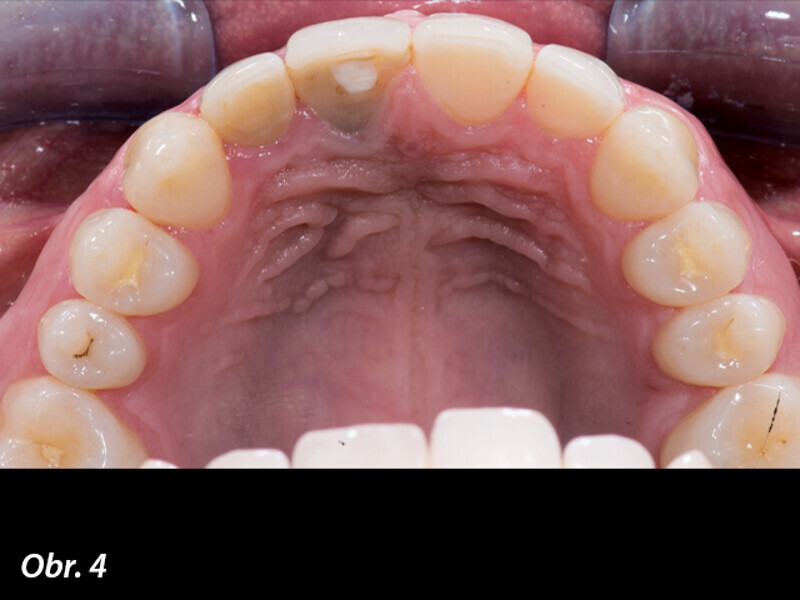

Management měkkých periimplantátových tkání pomocí kolagenní matrix a digitálního postupu